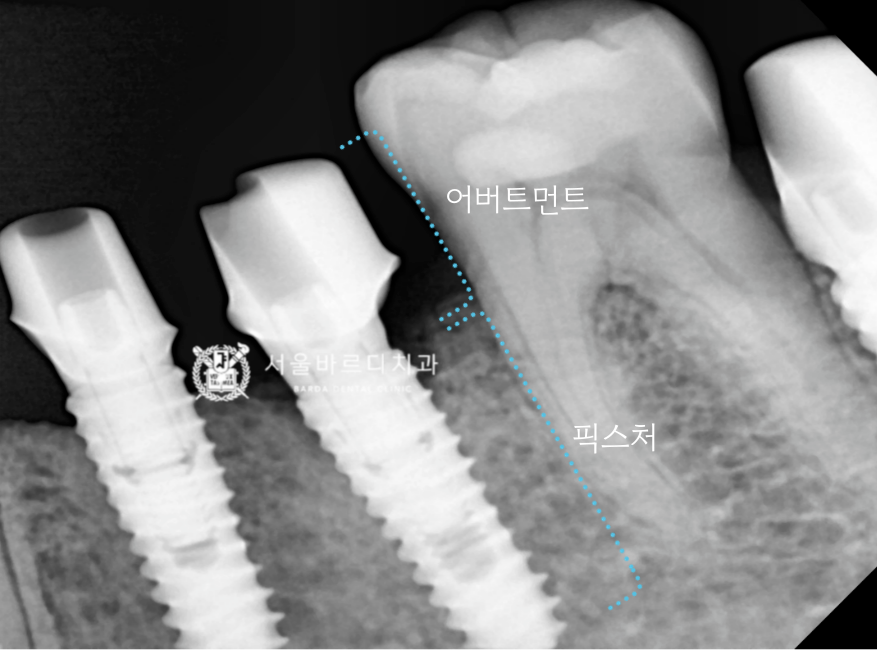

임플란트의 뿌리 역할을 하는

픽스처를 넣기 위해서 충분한 폭이 필요한데

이를 뽑은지 오래되어 치조골의 폭이

많이 좁아져 있었습니다.

스캐너로 픽스처와 잇몸의 위치를 기록한 덕분에

맞춤 기둥을 잘 맞게 만들어 올 수 있었고,

기둥을 체결한 다음 보철을 올려서 확인해 보니

맞물림도 잘 맞아서 바로 붙여드릴 수 있었습니다.

임플란트는 뿌리가 작고, 머리가 큰 가분수 형태라서

힘을 잘 견디고, 음식을 덜 끼게 하기 위해서

두 개의 크라운을 붙여서 스플린트 형태로

만들어 드리고 있는데요.

덕분에 식사하는 힘을 더 잘 받을 수 있어서

뿌리가 찢어지거나 보철이 깨지는 등의

문제를 줄일 수 있게 되었습니다.